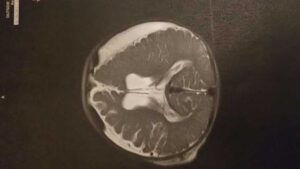

“My son was born on a Native American reservation in Montana back in October 2016. He was born and was just like any other baby. At five months old, he was rushed to the emergency room because something was not right. Once he arrived, it was determined that either his biological mother or father had shaken him. He had bleeding on both sides of his brain and both of his eyes had hemorrhaged. He was flown to Salt Lake City Children’s hospital to be stabilized and undergo surgery. He had a ventriculoperitoneal shunt placed to drain the blood and fluid from around his brain. This runs internally from the middle of his brain all the way down his right side into an open cavity near his stomach. He will have this shunt for rest of his life.

We are still dealing with the struggles of what the future may hold. He will probably have many doctors’ appointments throughout his life. He has to get MRIs frequently to monitor his progress of recovery. Currently, he only has one spot that has not recovered from his injury. This will impact his executive function skills such as problem solving, sequencing, organization, and critical thinking. He will always be in and out of therapies in order to meet his developmental milestones. He will probably need special education services in order to be successful in school. He will never be able to play contact sports due to his shunt. We will always worry about him any time he hits his head. All of this is stuff that we will have to deal with everyday, but we truly wouldn’t have it any other way. He has beat every goal we have set for him, and we know he will do great things.”